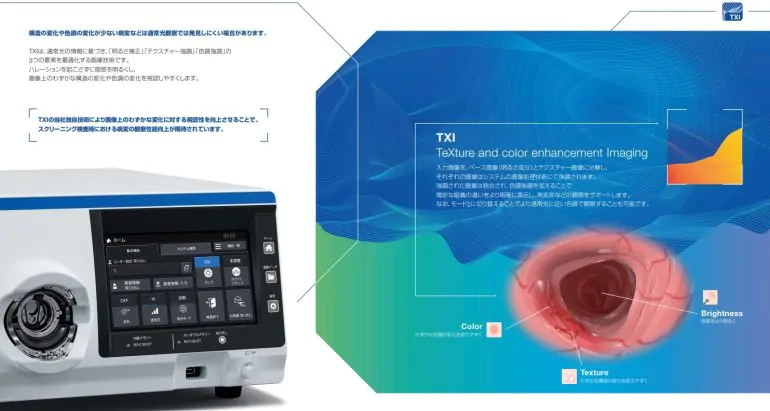

TXI(Texture and Color Enhancement Imaging)

色調の変化が小さい病変や凹凸の少ない平坦な病変は見つけにくいことがあります。この課題をクリアするために登場した「TXI(Texture and Color Enhancement Imaging)」は、画像処理技術によって病変をより見つけやすくすることを目指した画像強調技術です。

TXIは、粘膜表面の「構造」「色調」「明るさ」の 3 つの要素を最適化する画像強調技術です。通常光観察では見づらい画像上のわずかな色調や構造の変化が、TXI を活用することにより強調され、病変部などの観察性能向上に貢献することが期待されます。